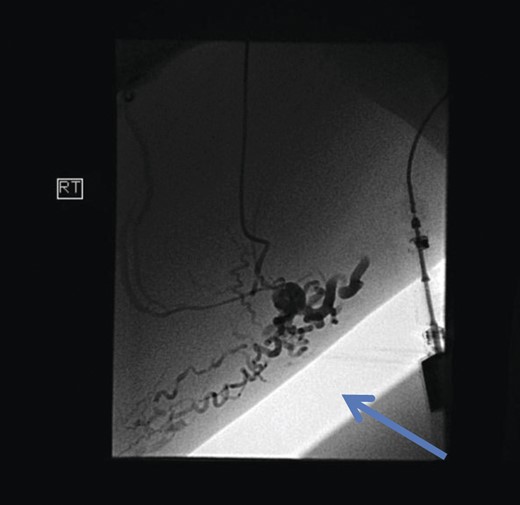

Initial investigations included duplex scan, followed by magnetic resonance scan. Duplex scanning demonstrated a competent sapheno-femoral (SFJ) and Sapheno-popliteal (SPJ) junctions bilaterally; however, did raise suspicion of a pelvic origin of the vulval varices with congested pelvic veins. Magnetic resonance venogram aided the diagnosis by demonstrating the communication of the vulval varices to the upper thigh veins with contribution from the internal iliac vein. In this case there was no evidence of ovarian varices (Fig. 1). Catheter venography was unable to confirm the contributing vein with certainty but computed pelvic venography showed a likely connection through the superficial external pudendal vein (Fig. 2).

Magnetic resonance venogram showing communication of thigh veins to vulval varices (blue arrow).